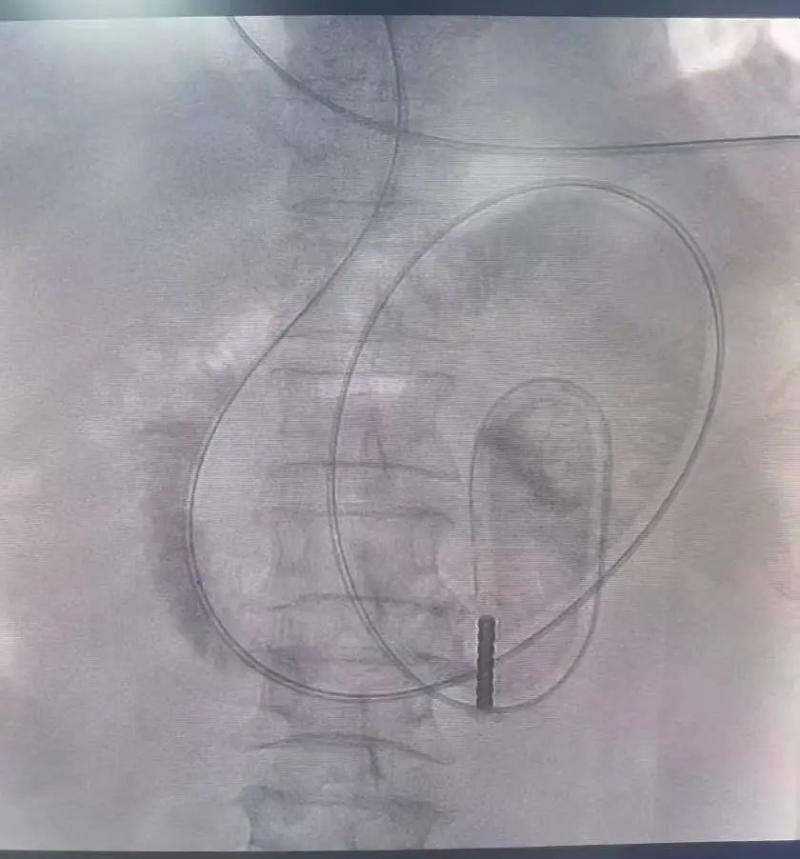

在數字減影血管造影(DSA)的實時監控下,張喆團隊將一根3米長的特制導管從陳伯鼻腔緩緩送入腸道。導管前端裝有可充氣球囊,注入造影劑后,在X光下形成清晰的標記點。借助腸道自身的蠕動,導管如“探路者”般蜿蜒穿過小腸褶皺,最終精準抵達梗阻近端。

文章配圖

△導管在介入導絲的引導下緩慢而安全的進入梗阻的腸管。